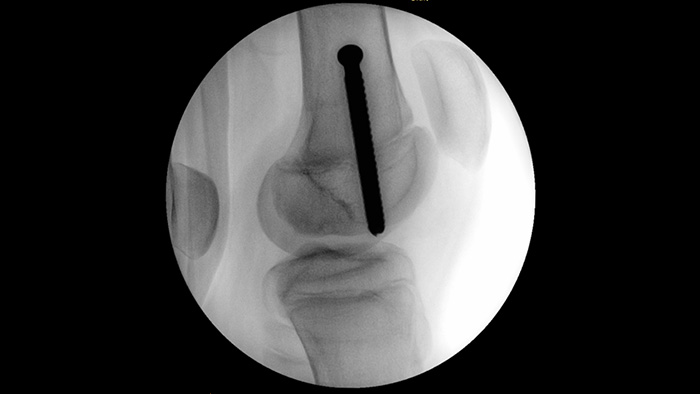

MetalSmart excluye automáticamente los artefactos metálicos causados por los implantes metálicos para proporcionar una mayor calidad de imagen y un control eficiente de la dosis para los procedimientos ortopédicos y para los pacientes con implantes metálicos, en comparación con los sistemas sin exclusión de metales. BodySmart favorece la obtención de imágenes correctas a la primera y la eficiencia de la dosis ya que adapta, de forma automática, el campo de medición a la zona de interés.